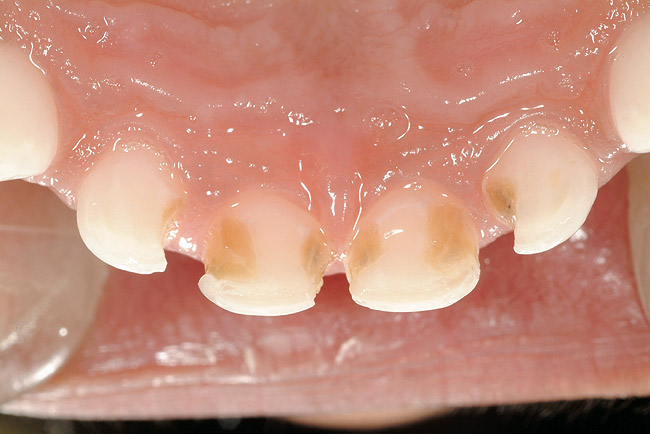

The characteristics of ECC (Figure 2) are:

1. It develops rapidly. Progression from the enamel into the dentin occurs in 6 months or less.

2. It affects the upper front teeth first. These teeth usually erupt at around 8 months of age.

3. Primary molars, which begin to erupt at about 12 months of age, are the next teeth to be affected.

4. Finally, the lower front teeth are affected when the disease becomes very severe.

As the condition worsens, white-spot lesions develop into larger caries lesions. The time frame from early decay to later decay can be as short as 6 to 12 months. At this point, the child may complain about toothache when extremely cold foods are eaten. As the caries process continues, the lesions will appear as brown/black collars around the gingival margin. The child will often begin to indicate the presence of pain.

The time frame from later to severe decay can be as little as 6 weeks. This is because once the decay penetrates through the hard outer enamel layer of the tooth and enters the dentin, it progresses very quickly.